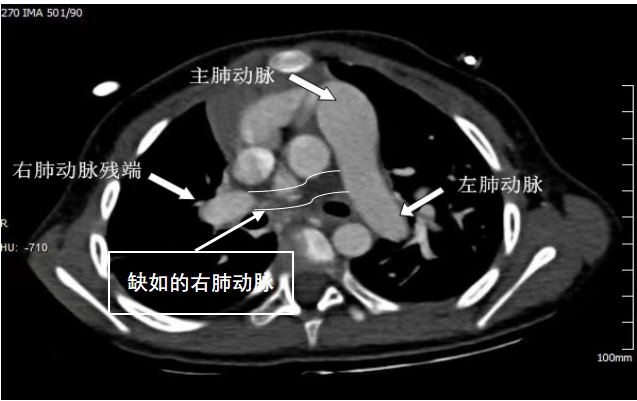

近日,兰大二院心脏外科为一名2岁双侧肺血不平衡先天性心脏病患儿成功实施了右侧肺动脉重建手术,同期矫治了房间隔缺损、动脉导管未闭及粗大的体-肺动脉侧支,患儿术后恢复良好,复杂先心畸形得到矫治,现已治愈出院。

在多学科医护人员的密切配合下,心脏外科主任吴向阳为患儿实施了手术治疗,术中游离出了体-肺动脉侧枝,剖开后形成新生的右肺动脉后壁,前壁运用了生物补片,完成了右肺动脉重建。术中,同期结扎了未闭的动脉导管,修补了房间隔缺损及反流的三尖瓣,完成了心内畸形的矫治手术。术后患儿转至CICU(心脏外科重症监护病房)进行观察治疗。

该手术优势在于采用自体血管组织重建右肺动脉后壁,使重建的右肺动脉具备一定的生长能力,最大限度地避免未来进行二次手术。同时,手术治疗后患儿原有严重的双侧肺血及肺动脉压力不平衡状态得到了有效矫治,患儿肺血及肺动脉压力回归正常。